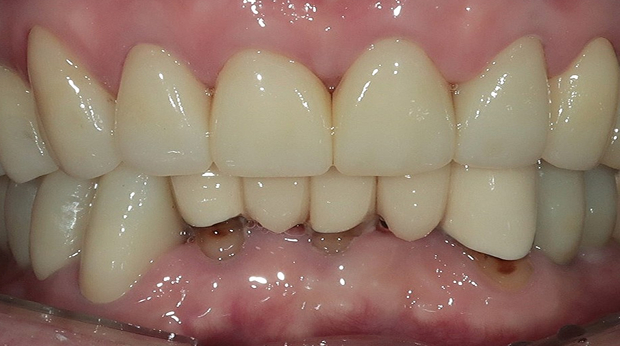

구강외과 진료

라미네이트

고난도 수술 진료